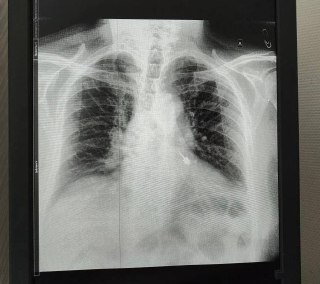

😨 В Подмосковье мужчина случайно проглотил стоматологический бур во время зубного лечения в частной клинике

Он незамедлительно обратился в районную больницу, где медики успешно извлекли инструмент из его левого бронха.

Сейчас с мужчиной все в порядке, его выписали, и он чувствует себя хорошо.